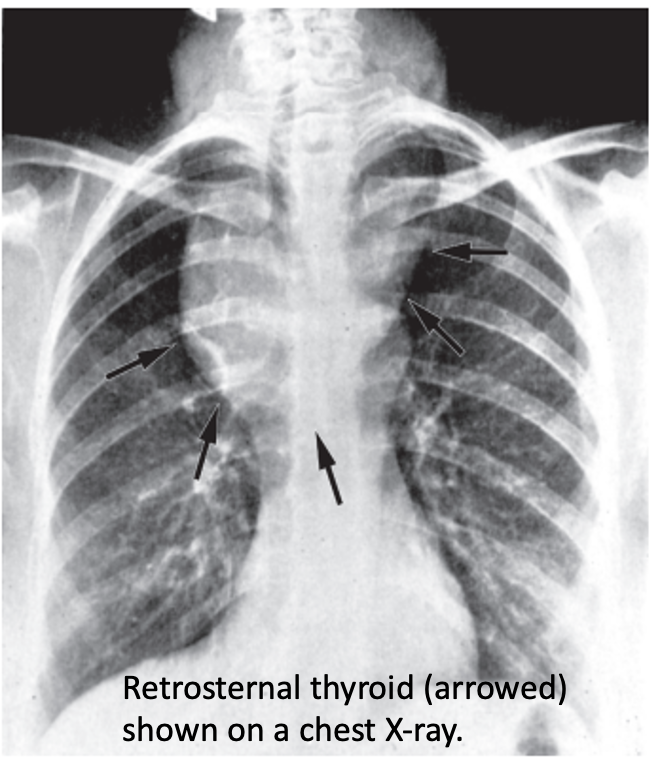

Pemberton’s sign is used to evaluate venous obstruction in patients with goiters. The sign is positive when bilateral arm elevation causes facial plethora. It has been attributed to a “cork effect” resulting from the thyroid obstructing the thoracic inlet, thereby increasing pressure on the venous system.